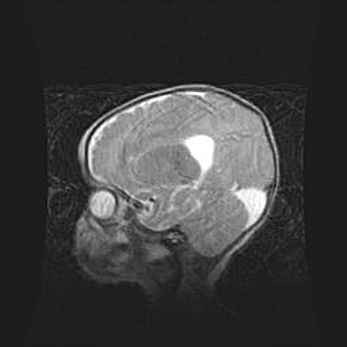

Аномалия Денди-Уокера. Признаки гипоплазии мозолистого тела.

Возраст: 5 месяцев 3 дня

Вес: 5550 г

Пол: мужской

Окружность головы: 39 см

Срок гестации: 40 недель

Аномалия Денди-Уокера – это порок развития головного мозга, для которого характерна триада симптомов: гипотрофия или аплазия червя мозжечка и/или полушарий мозжечка, расширение четвёртого желудочка с формированием ликворной кисты задней черепной ямки, гипертензионная гидроцефалия различной степени.

Гипоплазия мозолистого тела относится к дефектам внутриутробного этапа развития мозговой ткани, возникающим в процессе закладки структур головного мозга, что происходит на начальных этапах развития эмбриона.